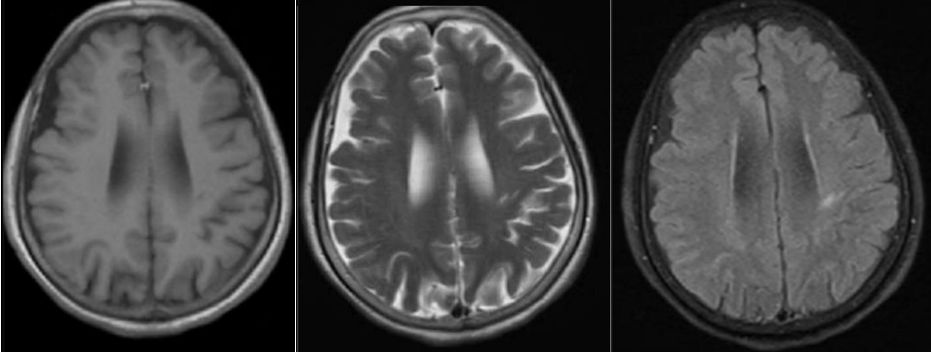

30岁女性,言语不清3年。

答案:肝豆状核变性。又称Wilson’病(WD),是一种常染色体隐性遗传的铜代谢障碍性疾病。主要是由于铜离子异常大量沉积于肝、脑、肾等组织,从而导致全身多系统多器官的损害,以神经系统症状、精神症状、眼部损害、肝脏损害等为主。神经系统最突出的症状是锥体外系症状,包括震颤、构音障碍、肌张力障碍、手足徐动症、共济失调等。构音障碍表现为声音低沉、含糊或嘶哑、缓慢或断续,严重时发不出声,是舌、唇、咽、喉和下颌肌肌张力增高所致。而肝脏的表现通常为肝功能损害、肝硬化、门脉高压症等,一般年轻患者居多。MRI表现为壳核、尾状核头和苍白球在T2WI上呈低信号,齿状核和红核亦可见T2WI为低信号。还可有不同程度的脑萎缩,如两侧壳核对称性裂隙,豆状核、尾状核、大脑皮质、脑干和小脑的萎缩。大小熊猫征为Wilson病的典型特征。